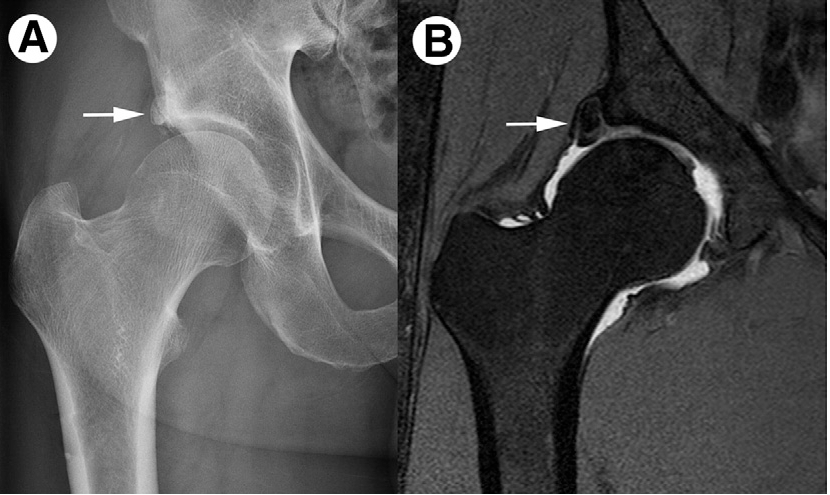

2.Pincer-тип

Избыточное нависание вертлужной впадины над головкой бедра, либо увеличение площади покрытия, либо ретроверсия/другие аномалии впадины. Из-за этого край впадины или губа ущемляются между головкой/шеей бедра и краем впадины.

- Рентгенография: выявление морфологии, утолщения, изменения формы.

- МРТ / МР-артрография: оценка состояния хряща, губы, мягких тканей, наличие сопутствующих повреждений.